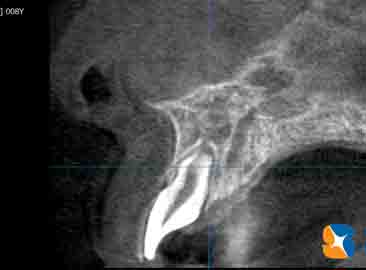

横からの断層で歯根周囲の骨の厚みをチェック

コラム「横からの断層で歯根周囲の骨の厚みをチェック」の画像